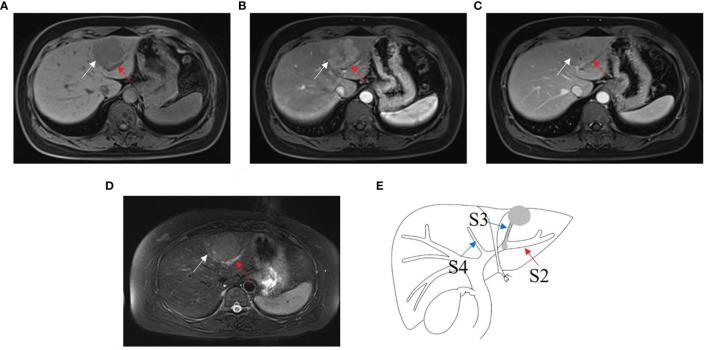

HCC patients with B1-B3 BDTT had more advanced tumor stages and adverse clinicopathological features. HCC lesions were detected in all patients, and intrahepatic bile duct dilation was observed in 28 (93.3%) patients with B1-B3 BDTT and 9 (1.43%) patients in HCC without BDTT. The intrahepatic bile duct dilation showed no enhancement at hepatic arterial phase (HAP) and no progressively delayed enhancement at portal venous phase (PVP), but it was more obvious at PVP on CT. In the reports of the 30 HCC patients with B1-B3 BDTT generated for the image when the scan was done, BDTT was observed in all 13 B3 patients and 3 of 12 B2 patients, but none of the 5 B1 patients. Fourteen patients were misdiagnosed before surgery. However, when using intrahepatic bile duct dilation in HCC patients as a potential biomarker for BDTT diagnosis, the sensitivity and specificity for BDTT diagnosis were 93.33% and 98.57%, respectively. The blinded reading test showed that intrahepatic bile duct dilation in CT and MRI scans could be for separating HCC patients with B1-B3 BDTT from HCC patients without BDTT.

The HCC lesions and intrahepatic bile duct dilation on CT or MRI scans are imaging features of HCC with BDTT, which might facilitate the early diagnosis of B1-B3 BDTT.

B1 - B3级BDTT的HCC患者肿瘤分期更晚,临床病理特征更差。所有患者均检测到HCC病灶,28例(93.3%)B1 - B3级BDTT患者及9例(1.43%)无BDTT的HCC患者观察到肝内胆管扩张。肝内胆管扩张在肝动脉期(HAP)无强化,门静脉期(PVP)无渐进性延迟强化,但在CT上PVP时更明显。在为扫描图像生成的30例B1 - B3级BDTT的HCC患者报告中,13例B3患者及12例B2患者中的3例观察到BDTT,而5例B1患者均未观察到。14例患者术前误诊。然而,将HCC患者肝内胆管扩张作为BDTT诊断的潜在生物标志物时,BDTT诊断的敏感性和特异性分别为93.33%和98.57%。盲法阅片测试表明,CT和MRI扫描中的肝内胆管扩张可用于区分B1 - B3级BDTT的HCC患者和无BDTT的HCC患者。

CT或MRI扫描上的HCC病灶及肝内胆管扩张是BDTT的HCC的影像学特征,这可能有助于B1 - B3级BDTT的早期诊断。